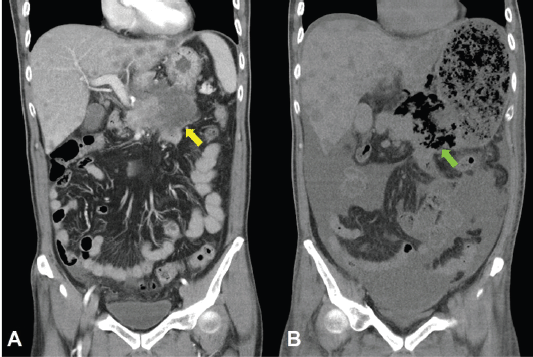

Unfortunately, a catastrophic event did happen 2 days after finishing the first course of chemotherapy. The patient experienced sudden onset of intolerable abdomen pain with hypoactive bowel sounds, muscle guarding, and definitely apparent rebounding pain. An emergent non-contrast CT scan gave a picture of distended stomach fully filled with foods, irregular mottled gas collections between stomach and duodenum, ascites accumulation, and free air in the abdomen cavity, leading to an impression of gastrointestinal tract perforation with the perforation site clearly seen (Figures 6–8). In comparison with CT scan performed at initial diagnosis, it seemed that a severe necrotising tumour lysis induced by chemotherapy, morphologically resembling emphysematous pancreatitis [14–16], could explain the whole scenario logically.

Figure 7. CT scan of the abdomen, coronal view. A. June 8, 2019. Yellow arrow: the huge gastric tumour. B. July 3, 2019. White arrow: gastric perforation site. Green arrow: Necrotising tumour lysis simulating emphysematous pancreatitis.

Figure 8. CT scan of the abdomen, coronal view. A. June 8, 2019. Yellow arrow: the huge gastric tumour. B. July 3, 2019. Green arrow: Necrotising tumour lysis simulating emphysematous pancreatitis.